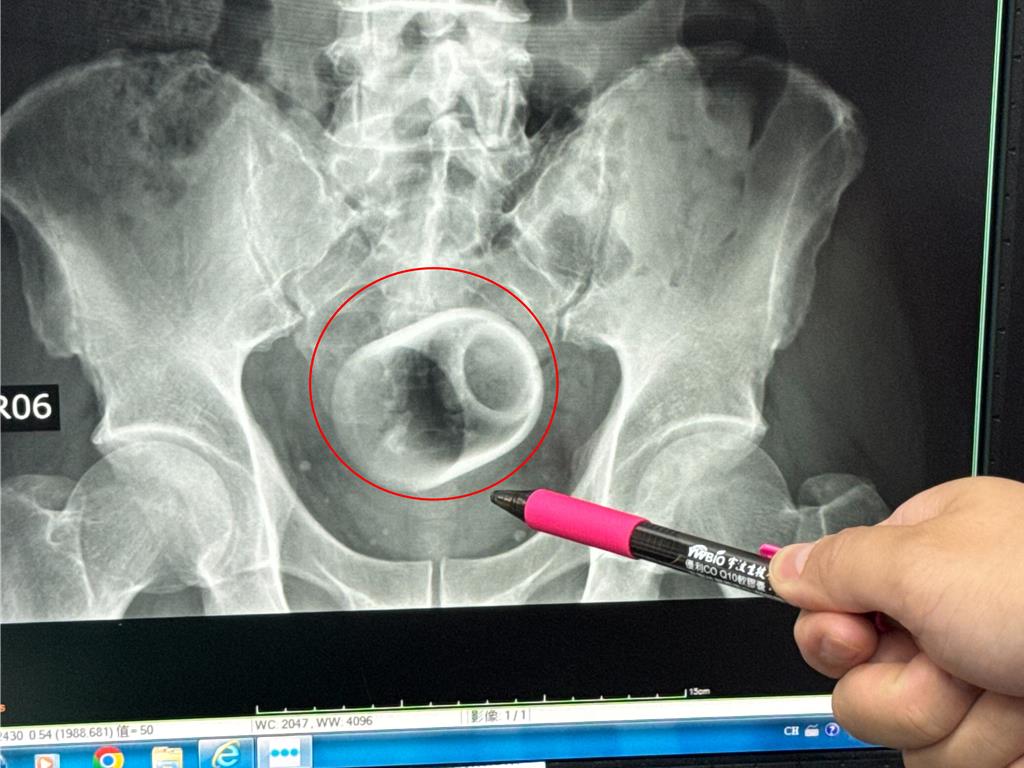

該名患者到院時稱,已經3天無法大便很困擾,害羞不敢提及自己肛門塞了一個杯子,經過X光攝影,可見骨盆腔內有一個直徑約6公分、高約8公分的杯子,杯口朝下,自己當時見狀嚇一大跳,立即安排進手術室,要把杯子拿出來。

醫師起初使用器械要把杯子夾出來,但因杯子光滑無法施力,加上杯身全被大腸包住,部分腸子缺血也造成壞死,後來再使用腹腔鏡,依舊無法順利取出,也擔心把杯子夾碎,傷及患者或造成感染風險,最後只好在肚子上動刀畫開腸子,手術總共歷經2個多小時,最終才取出杯子,同時做好一個人工造口,讓患者能夠暫時解便。